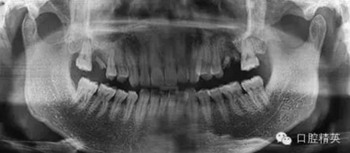

拔除前曲斷

X線顯示左上頜6殘根,慢性根尖周圍炎波及上頜竇底,行拔除殘根處理,囑術(shù)后常規(guī)消炎。